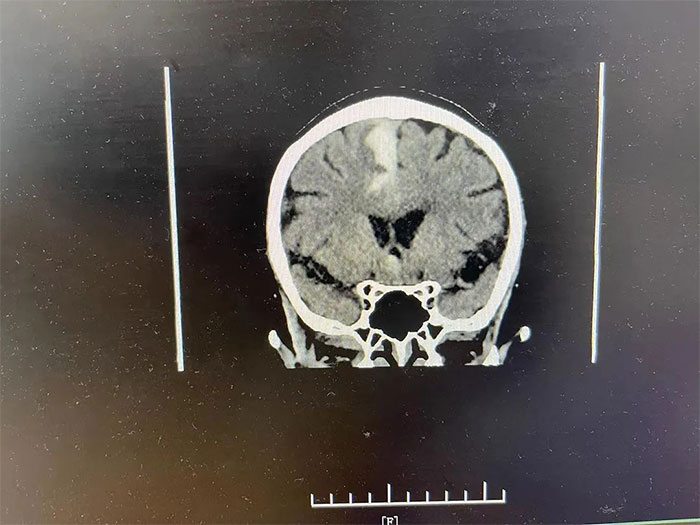

▲ 通過治療,出血已基本吸收

通過科學(xué)、合理用藥,改善腦循環(huán)、腦代謝;營養(yǎng)神經(jīng),改善神經(jīng)功能。同時,為吳阿姨施以精研的中醫(yī)“紫荊”針灸療法,疏通筋絡(luò),解除腦血管痙攣,以加速組織對顱內(nèi)出血的吸收,促進(jìn)各項腦神經(jīng)功能的恢復(fù)。接受治療不到半個月,吳阿姨的病情就獲得了顯著改善,身體狀況也明顯好轉(zhuǎn)。